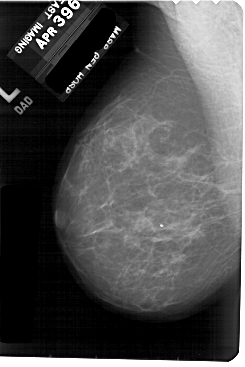

A_1886_1.RIGHT_CC

LEFT_MLO LINES 5491 PIXELS_PER_LINE 3661 BITS_PER_PIXEL 12 RESOLUTION 43.5 NON_OVERLAY